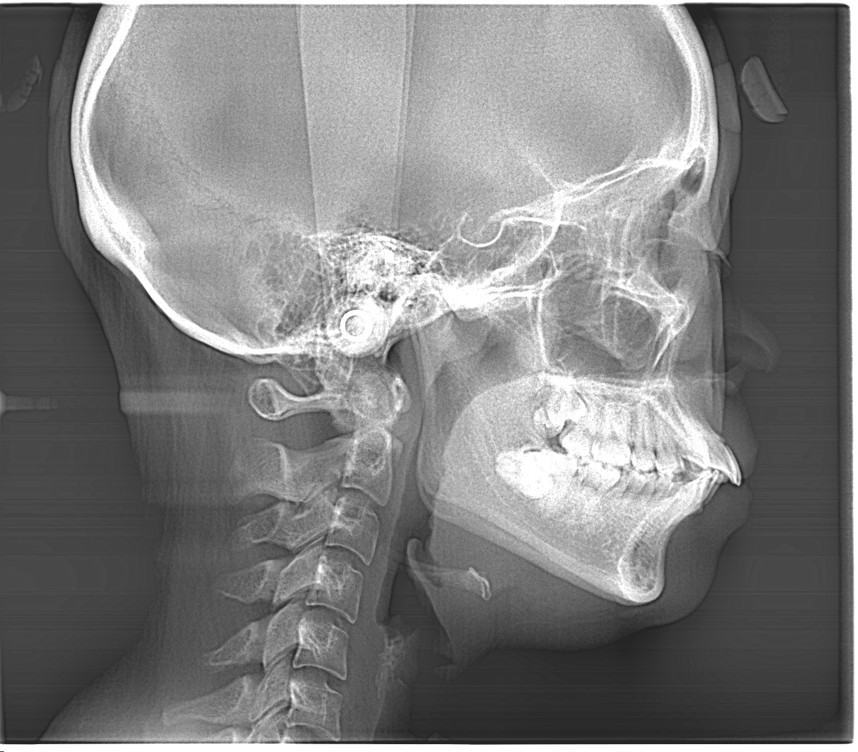

Before

この方の場合は上下の骨格の関係も二級関係(上顎が若干前・下顎が若干後ろに位置している)もありましたが、最も顕著だったのは、上下の前歯の歯の軸が上下ともに前に倒れていることでした。

注目していただきたいのは前歯の角度です。

上下の前歯が作る角度(インターインサイザルアングル)が99°でした。

99度ってどうなの?」と思われるかもしれませんが、理想的な美しさとされる角度は約120度〜130度と言われています。つまり、99度というのは「前歯がかなり外側にパタンと倒れて、突き出している状態」なんです。

この角度が深くなる(120〜130度に近づく)ことで、唇がスッと中に入り、横顔のEラインが整います。数字で見ると、矯正でどれだけ歯の土台から角度が変わったかが一目瞭然です。